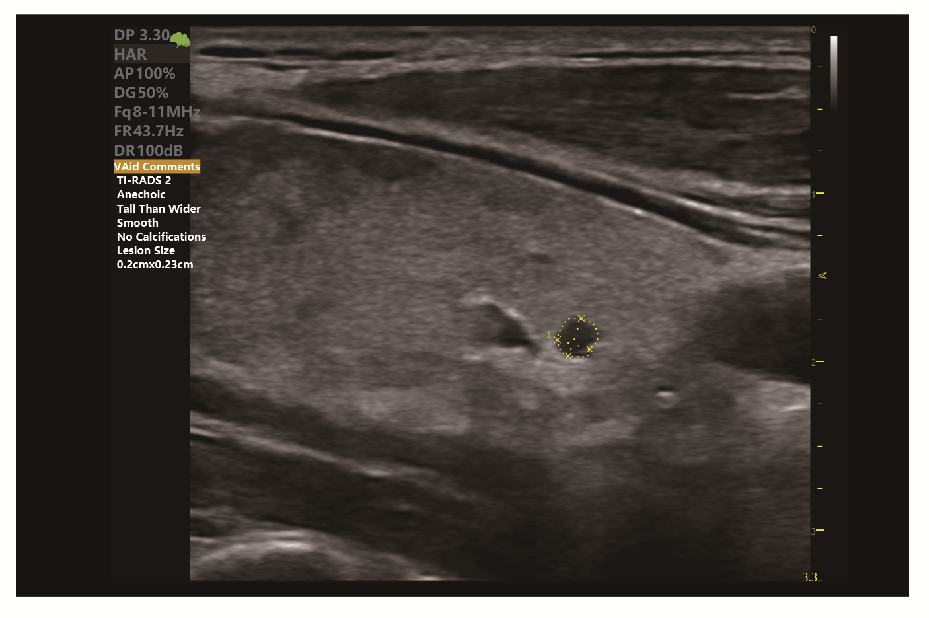

• VAid Thyroid з TI-RADS категоризацією

• VAid Thyroid - виявлення вузлів щитовидної залози з категоризацією за TI-RADS та створенням звітів

Клінічні зображення, що демонструють якість діагностики та можливості обладнання

Клінічне зображення 1